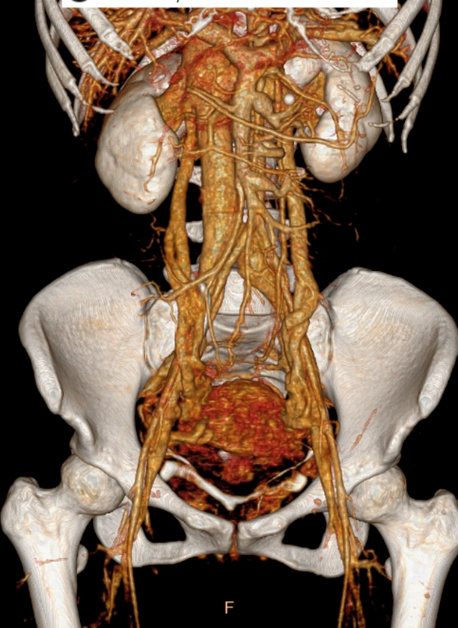

核心突破:将 May-Thurner 综合征(髂静脉压迫)、Nutcracker 综合征(左肾静脉受压)等纳入统一病理生理框架;

共识:PeVD 属于血管外科疾病,经典 PCS 仅为其中一种表现形式。

CTV提示双侧卵巢静脉及盆腔静脉扩张迂曲显著

经阴道超声、CTV:最宽处内径分别约0.59cm(左侧)、0.33cm(右侧),可探及返流血流信号